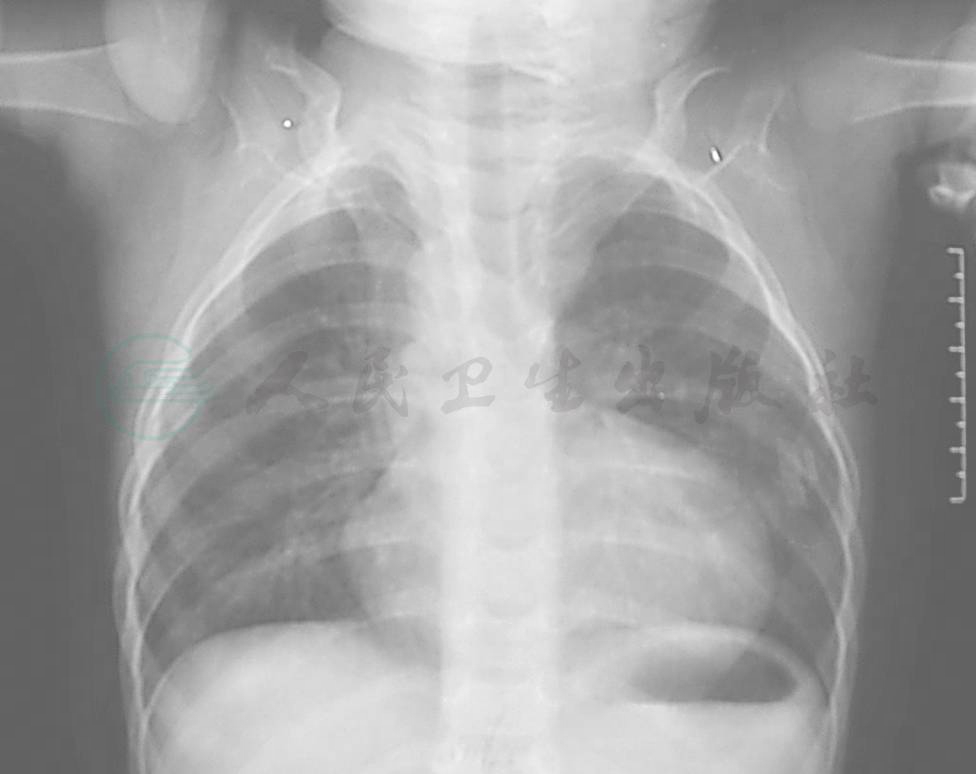

肺野异常清晰,肺动脉总干弧不明显或凹入,右心室增大,心尖向上翘起,在后前位片上心脏阴影呈木楔状(如横置的长方形)。该患儿可见右位主动脉弓,可发生在近1/4的患者(图2)。

图2 X线胸部平片